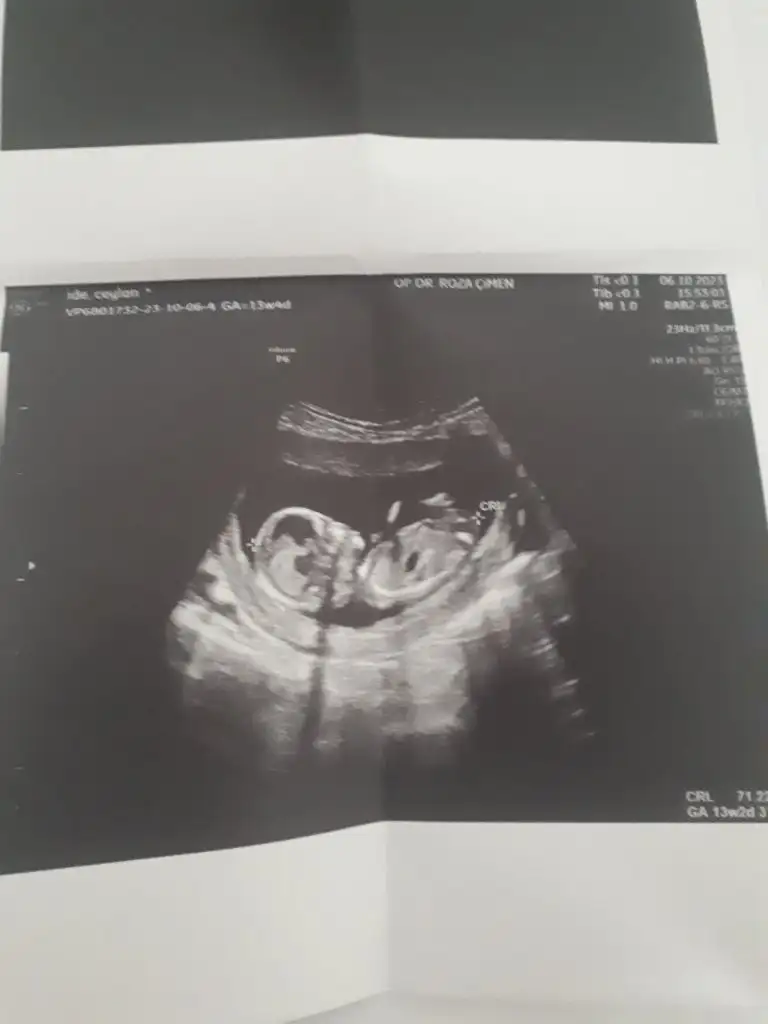

Havalianne__ Havalianne__ canım benimkine de bakar mısın 11+0 haftalık

• 1000121754.webp

1000121754.webp

25,9 KB · Görüntüleme: 80

• 1000121753.webp

1000121753.webp

21,8 KB · Görüntüleme: 88